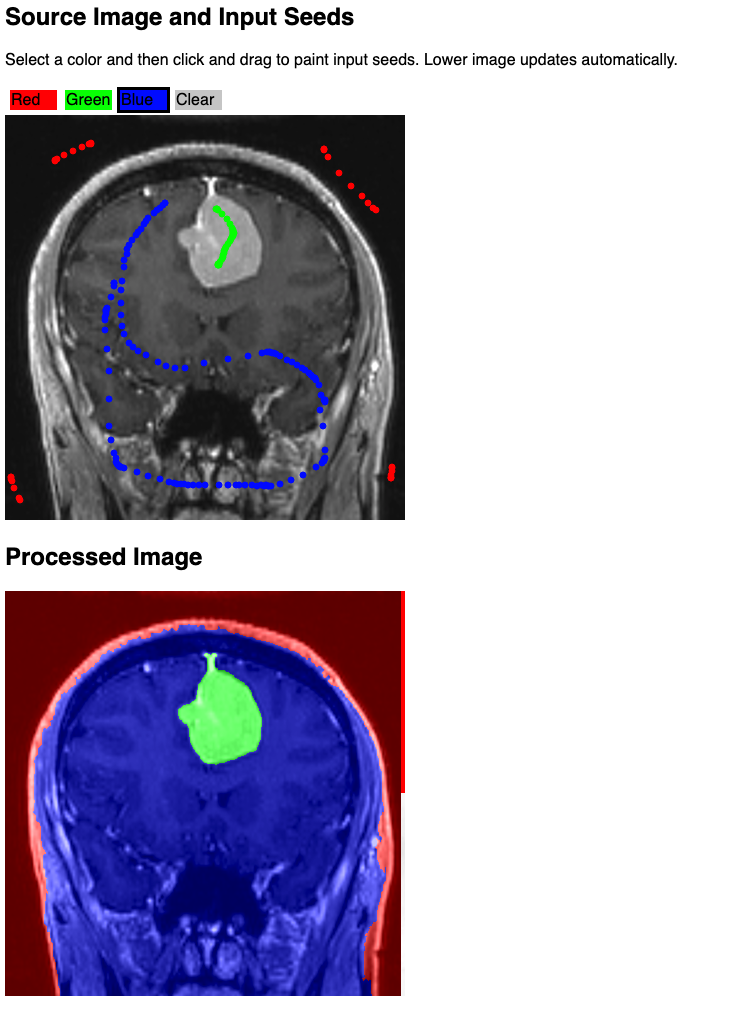

- Prototype implementation:

Background and References

- http://pieper.github.io/sites/glimp/index.html